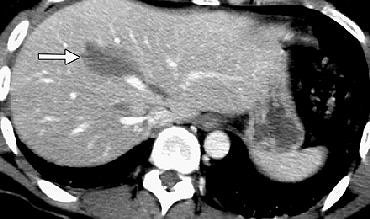

| A 22-year-old woman in the first trimester of pregnancy had sustained blunt abdominal trauma and subsequent splenic laceration in a motor vehicle collision. After US was performed, the patient was taken immediately to the operating room for laparotomy. Above, longitudinal US image of left upper quadrant reveals perisplenic free fluid (arrow) and abnormal-appearing splenic parenchyma (S). Below, longitudinal US image of pelvis shows free fluid (FF) superior to the bladder (BL) and gravid uterus (U). |

| Figure 3a-b, Richards JR, Ormsby EL, Romo MV, Gillen MA, McGahan JP, "Blunt Abdominal Injury in the Pregnant Patient: Detection with US" (Radiology, 2004; 233:463-470). |